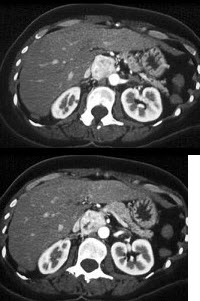

8、单项选择题

此两患者患同种疾病,如图所示,最可能的诊断为()

A.肝囊肿

B.肝癌

C.血管瘤

D.胆汁性囊腺瘤

E.肝脓肿

点击查看答案